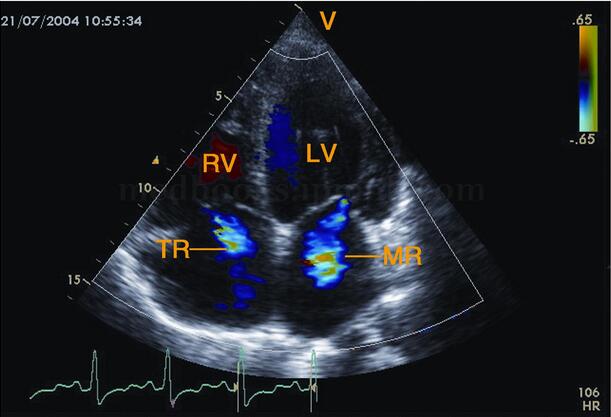

(2)合并多瓣膜反流,最常见于二、三尖瓣、肺动脉瓣(图2‐1‐189)。

图2‐1‐189 心尖四腔心切面彩色多普勒图像收缩期左、右房内出现蓝色稍花血流束